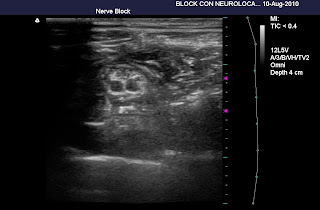

IMAGEN INUSUAL DEL PLEXO BRAQUIAL

Rara imagen de ecografia del plexo braquial donde se muestra el tronco superior y medio despues de un bloqueo interescalenico bajo con 30 ml de Bupivacaina 0.25% para una artroscopia de hombro

Dr. Willy Orcada Garcia